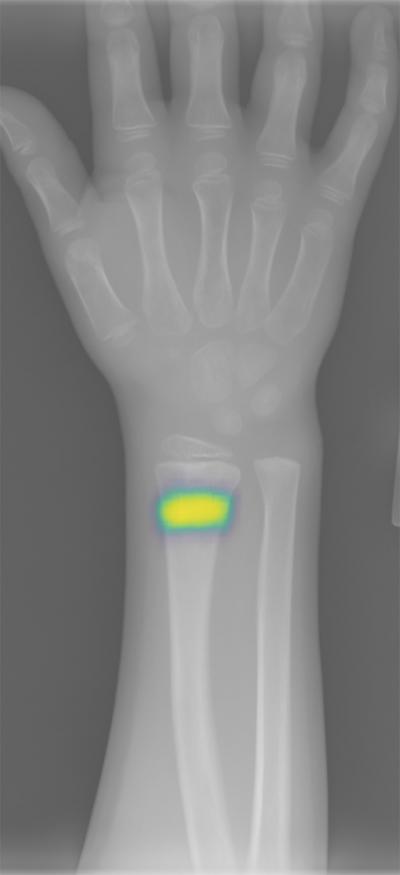

Researchers report that a deep neural network designed to identify fractures in radiographs that was trained using 135,409 annotated radiographs from 18 senior orthopedic surgeons helped emergency department clinicians reduce the rate of radiograph misinterpretation by 47%, a result demonstrating how deep neural networks, trained by experienced specialists, can transfer expertise to generalist clinicians.

Article #18-06905: "Deep neural network improves fracture detection by clinicians," by Robert Lindsey et al .